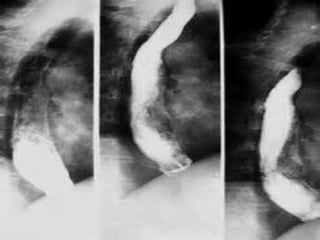

 El carcinoma del esófago se observa de

preferencia en el tercio inferior (40%), seguido

del tercio medio y del tercio superior.

Macroscópicamente puede ser de forma

infiltrativa o ulcerada. Produce estenosis y

obstrucción.

 El carcinomadel esófago se observa de preferencia en el tercio inferior (40%), seguido del tercio medio y del tercio superior. Macroscópicamente puede ser de forma infiltrativa o ulcerada. Produce estenosis y obstrucción.